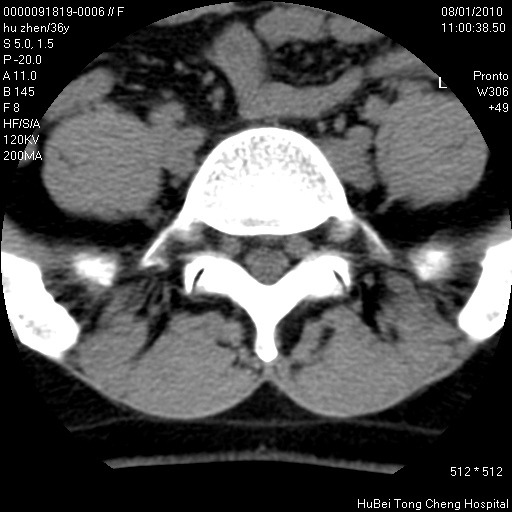

患者 女,36岁。右侧腰腿痛半月余。腰骶椎mr平扫偶然发现骶椎异常信号。

临床诊断:1)腰椎间盘突出症。2)骶椎肿瘤性病变?

骶椎ct平扫(层厚、层距均为5mm),图像如下:

考虑s1骨纤维异常增殖症。